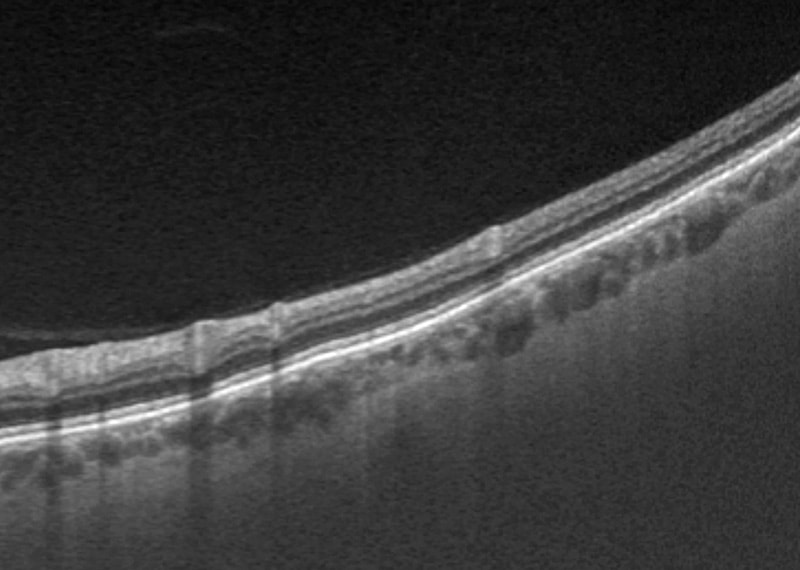

UWF OCTにより、周辺部のOCT撮影も可能

optomap®の合成カラー画像と 上方、中心、下方ラインのスキャン画像